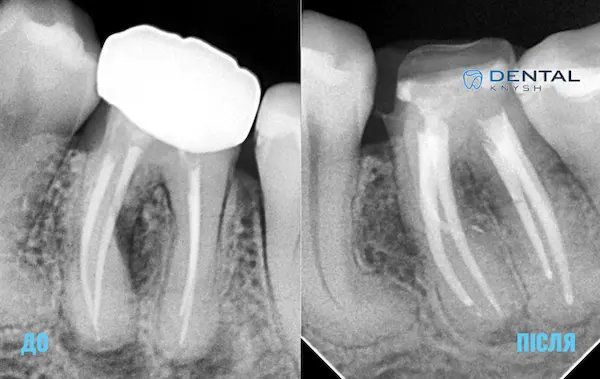

Фото-звіт ендодонтичного лікування, до/після, 2026-04-15